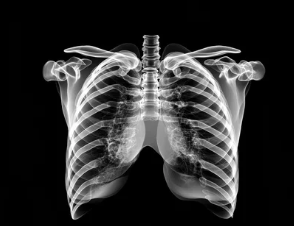

폐기흉(기흉, Pneumothorax)은 폐에 공기 주머니(기낭)가 터지거나 손상되면서 공기가 흉강(가슴막)으로 새어나와 폐가 수축하는 질환이다.

3. 폐기흉의 치료 방법 – 경미한 경우 & 중증 치료 차이

② 중증 폐기흉 – 흉관 삽입(공기 배출 치료)

✔ 폐가 심하게 눌려 있거나 호흡 곤란이 심할 경우, 흉관 삽입이 필요

✔ 가슴에 관을 삽입하여 폐 주위에 찬 공기를 배출(흉관 삽입술)